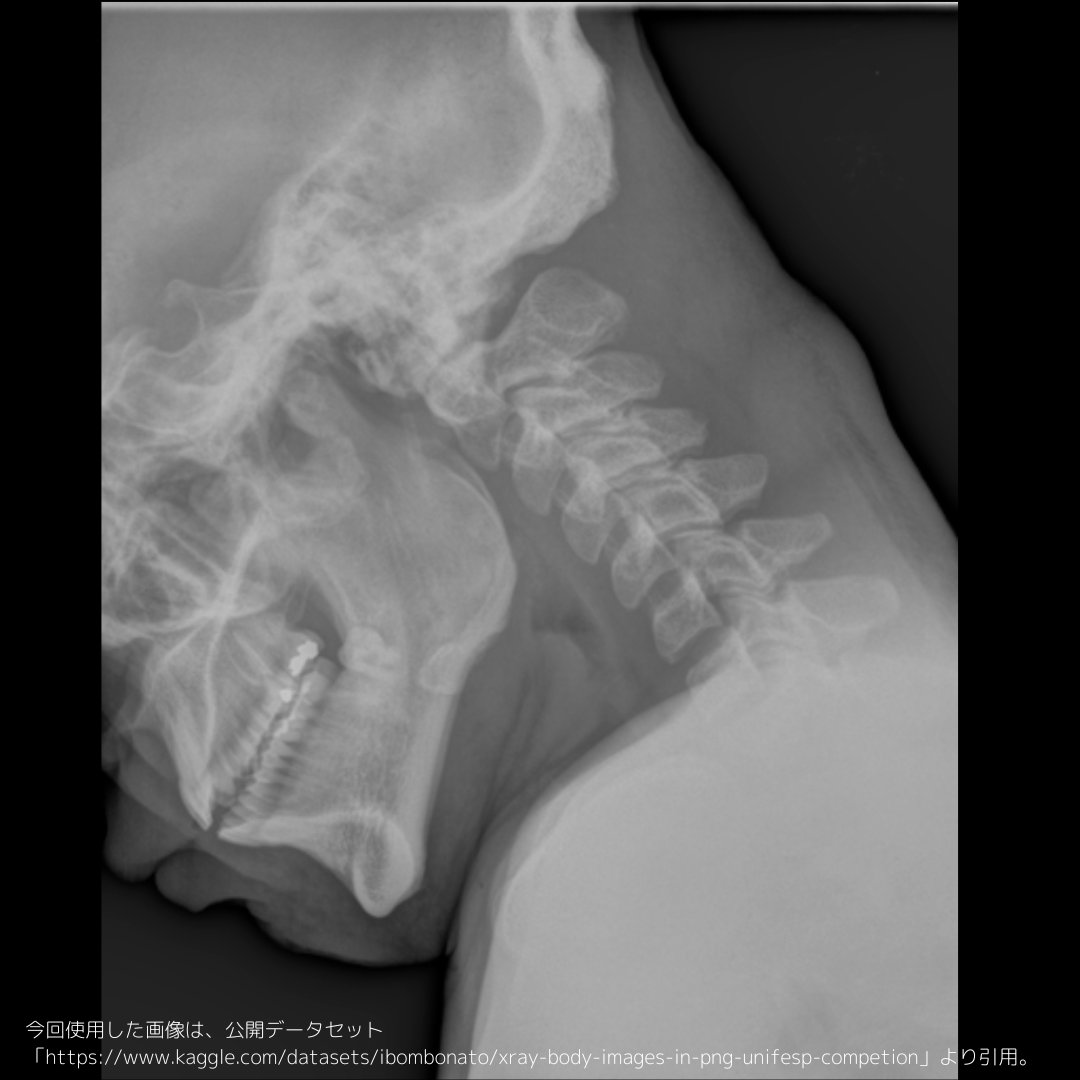

頸椎側面撮影➁ 左右の顎関節「がくかんせつ」のずれを見ると、側面の度合い(側面性)が分かりやすい。 真の側面にできると、左右の顎関節も重なって、椎間関節の腔もずれなく綺麗に見えます!(理想論) 実際は、この画像みたいなのが多いけど、、

左右の顎関節「がくかんせつ」のずれを見ると、側面の度合い(側面性)が分かりやすい。

真の側面にできると、左右の顎関節も重なって、椎間関節の腔もずれなく綺麗に見えます!(理想論)

実際は、この画像みたいなのが多いけど、、